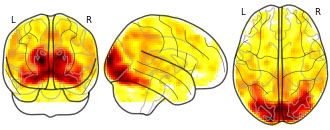

"name": "Multi_VBMsmaller_fMRIenhanced",

"description": "Multi-modal analysis in BPD. Brain regions exhibiting smaller gray matter and enhanced activation during emotion processing in BPD compared to healthy controls. Note: Results were thresholded at p<.0025. Note2: Results were updated (see Erratum for this publication).",